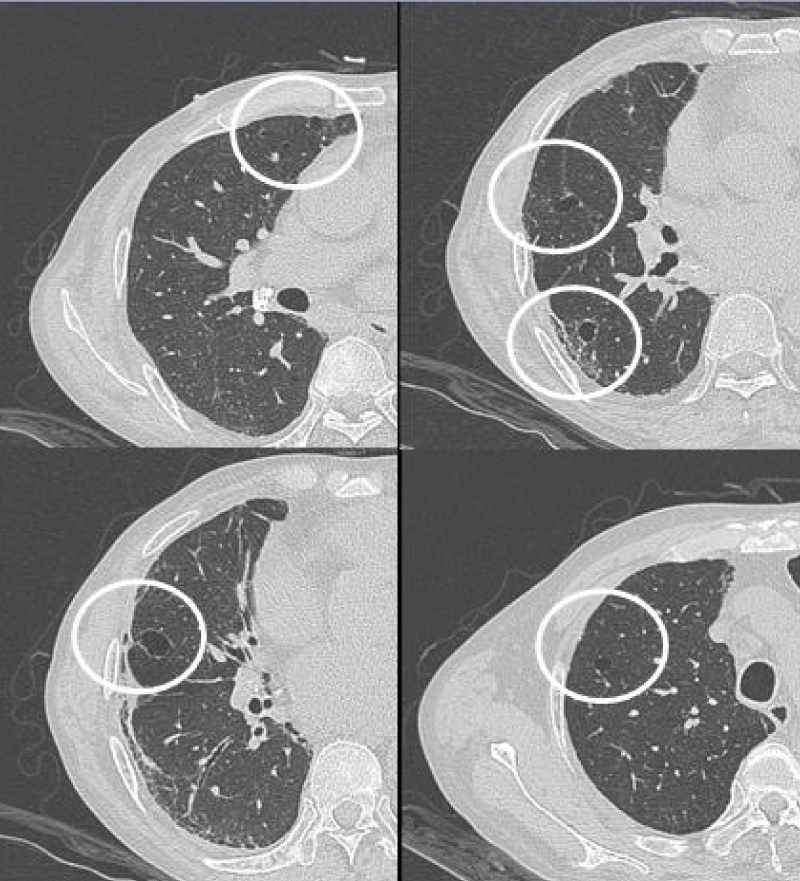

HRCT images

The most common presentation on HRCT were ground-glass opacities, showed 79.3% (92 patients). Secondly, 74.1% patients showed interlobular septal thickening, followed by reticular opacities(58.6%), intralobular interstitial thickening(45.7%), mediastinal lymph node enlargement(36.2%), nodules(30.2%), honeycomb cysts (29.3%), traction bronchiectasis(21.6%), stripes(17.2%), pleural thickening(14.7%), pleural effusion(10.3%), dilation of the esophagus(6.9%), emphysema(6.9%), bullae(5.2%), consolidation(5.2%), subpleural line(0.9%) (Figures 1-9).

Figure 1: Ground-glass opacities.

Figure 7: Different levels HRCT images from a 65 year-old male considered as NSIP pattern.

The most common pattern in SSc-ILD was NSIP, accounted for 71.6% (83 patients); secondly was UIP, accounted for 25.9%, and 3 patients presented consistent with LIP.

Histopathologically, NSIP was characterized by a uniform appearance of varying amounts of interstitial inflammation and fibrosis, and divided into cellular pattern (cNSIP) and fibrotic pattern (fNSIP). The typical finding of cNSIP was diffuse inflammatory cell infiltration without obvious fibrosis; fNSIP characterized by diffuse thickening of the alveolar walls with or without inflammatory cell infiltration [18]. On HRCT, cNSIP showed ground-glass opacities mainly, reticular opacities and traction bronchiectasis were relatively infrequent, without honeycombing; patients with fNSIP had few honeycombing, as well as greater extent of ground-glass opacities, traction bronchiectasis, and opacities than those with cNSIP [19].